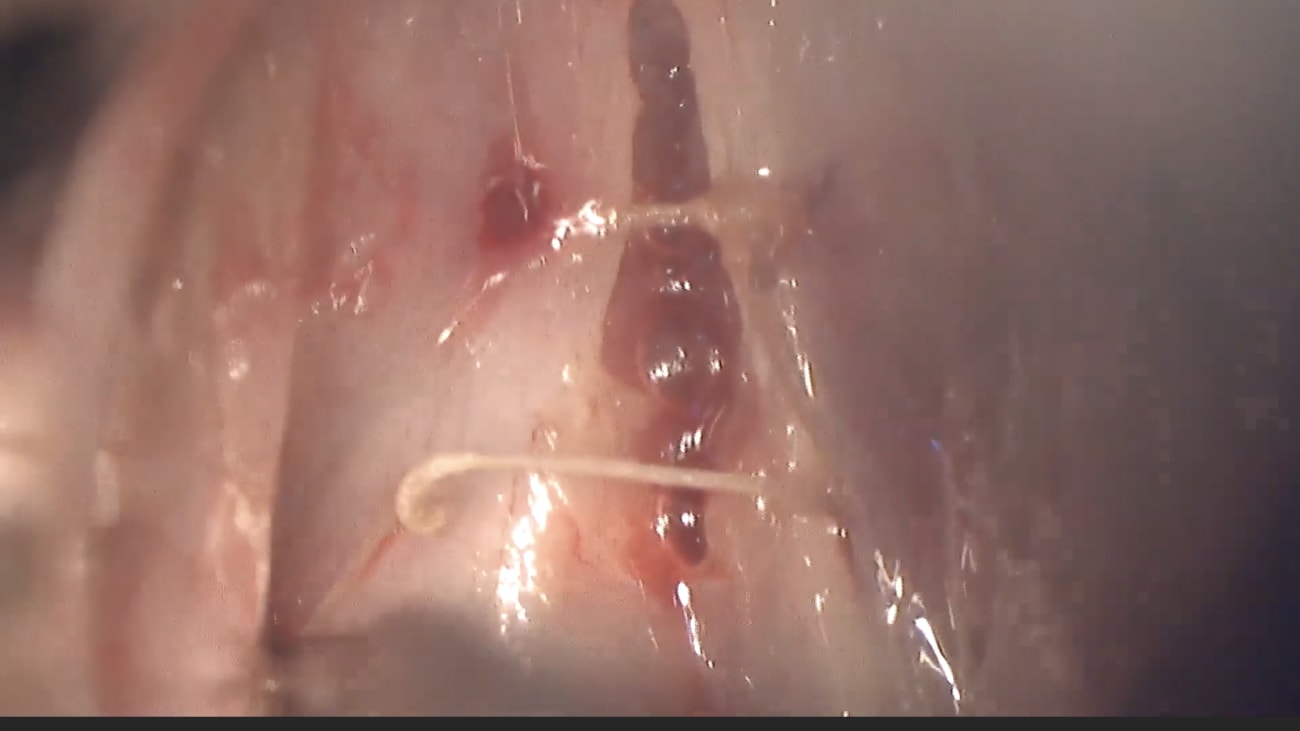

The Mount Sinai Oto Laryngology Surgical Video Series presents Wendler gloop plasty or voice feminization surgery. This procedure is performed by our department, laryngologist. For those patients desiring a higher fundamental frequency in pitch, we will resect the anterior one third of the vocal fold, thereby creating an anterior glottic web and shortening the functional vibratory length if done with attention to symmetry. This procedure reliably increases vocal pitch without significantly changing vocal roughness or breaths. This is a schematic diagram of a Coronal cross section through the vocal folds. The important structures are labeled zooming in an incision is made through the epithelium on the upper lip region. The vocal ligament incised along the medial surface and dissected off the underlying thyro retinoid or T A muscle. This is also known as the vocalis muscle. The T A muscle fash is left intact. If possible, we create an inferiorly base flap of mucosa at the inferior arcuate line to decrease the likelihood of co-opting the mucosa and lessening the risk of granulation tissue formation under suspension microlaryngoscopy. A co two laser with a pattern generator is used to measure the distance from the vocal process to the anterior comma the goal is to respect 45% of this length. We start with an incision in the upper lip that is less than 40% as it will expand during surgery as the tension is released. After the initial mucosal incision, the laser line is shortened to 1.5 to 1.8 millimeters for the dissection. An instrument is used to attract the incise portion immediately to gain countertraction. The amount of vocal fold to be removed is the anterior one third, a similar procedure is performed on the right vocal fold to a similar depth. Transverse posterior cuts are made first on the right and then on the left retracting the tissue immediately gives one enough traction to be able to dissect between the T A muscle and the vocal ligament first on one side and then on the other. Once the muscle is exposed, we create the flap at the inferior arcuate line anteriorly, the tissue is removed on block, pulling it off the anterior macula flavum. This is a 70 degree endoscopic view showing the extent of resection. The endoscope is looking anteriorly towards the anterior comma. The tissue has been removed down to the level of the vocal or T A muscle. Next four vir sutures are placed to reapproximate the raw surfaces and to create an anterior glottic web. This diagram shows the entry points of the four sutures. It is critical to have anterior and posterior symmetry as well as lateral symmetry. The four color coded labels standing for left anterior, left posterior, right, anterior and right posterior will correspond to a later diagram. This schematic will show one of the two sets of su placement. The needle is brought through the height of the entire right vocal fold with the sutures then brought back up through the Lagos. The same is done on the left side and the loose suture ends are tied together to form a knot. This nod is then pushed down inferior to the vocal folds, bringing the two sides together toward the midline. The sutra needles are then cut and the free ends are used to tie another knot. This knot is then pushed down tightly and the free edges of each vocal fold are brought in close proximity. Now, let's see it. In practice, the left anterior suture is placed and left to hang on the Larios cope to be tied later. Then the right anterior suture is placed and again left to hang on the Lagos cope. The left posterior suture is then placed and then the right posterior. At the end of suit placement, there is a web of sutures hanging off the larios cope, they should be well organized. However, so that one can keep track of what goes where the colors and text labels correspond to the earlier diagram. The arrows represent the direction that the sutras are coming in. All sutures are passed superior to inferior through the vocal fold. And then are pulled out through the larynx. The end marks the end with the needle on it. The matching symbols are the ends that will get tied together. The stars and circles represent the two inferior knots below the vocal folds. These are tied first. The hexagons and rectangles are the superior sutures and will be cinched down last. This shows the tying of the anterior inferior knot or the green start to the pink star. From the prior diagram, the needles have been cut off. A two handed surgeon's knot is thrown onto an assistant's finger followed by two subsequent single throws. It is important that all knots are square. The sutures are cut and this knot is passed down below the vocal folds. The same procedure is done with the posterior inferior knot and is not shown here. Next, tying of one of the superior surface knots is shown again. A two handed square surgeon's knot is thrown, it is then pushed down with an endoscopic knot pusher and subsequently forceps. It is tied down tightly. The same thing is done for the posterior superior knott. Generally speaking, it is important not to leave any exposed muscle as it makes patients prone to forming granulation tissue. As shown here in a different patient aligning the upper and lower masses is very important as shown here. This is an early postoperative stroboscopic exam from our patient showing the expected appearance. An anterior web has formed without granulation tissue this is a three month stroboscopic exam showing a well formed mature anterior glottic web speech therapy with a specialized speech language pathologist will be key to achieving the desired outcomes.